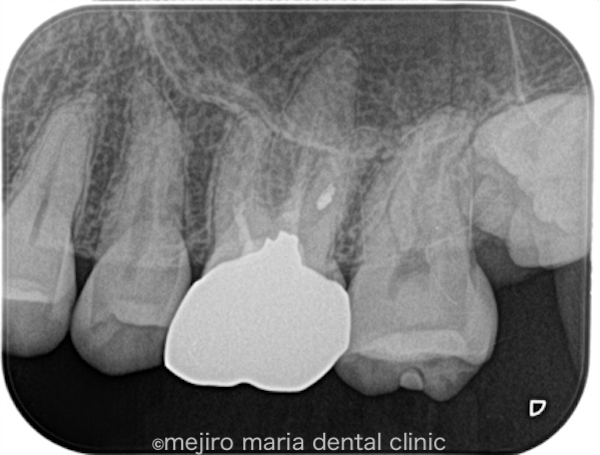

治療後の様子

今後は通常と同じように2年間の経過観察を行い、治療の経過を確認していく予定です。

また、当院では根管治療後2年間の経過観察によるフォローアップと、5年間の被せ物の保証でしっかりと予後経過を確認していきます。